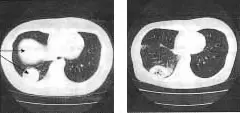

I was diagnosed with esophageal cancer when I visited the hospital in May 2008 for severe fatigue. I was told that the cancer was stage 4a and was inoperable. As a result, I was treated with two cycles of chemotherapy and radiation for two months. On August 5 th , I heard about the Garden Clinic and was admitted on August 14 th .I was treated with the hot gemstone mat, hormesis hot stone therapy, vitamin C and germanium shots.

I decided to purchase the hot gemstone mat and was treated twice a day at 70 degrees during the day and normal

Before treatment, whole body CT, arrow points the tumor

temperatures during the night. I took three kinds of supplements as well.

When I visited the hospital again in August, I was told that my cancer had improved significantly.

When they decided to biopsy my esophagus, I was told that my cancer had completely disappeared. I was extremely surprised. I am very healthy now. I cannot believe what has happened to me.

Stated using infrared mat since 2008. 7. 14

Lung cancer 2008. 2. 22 2008. 8. 1